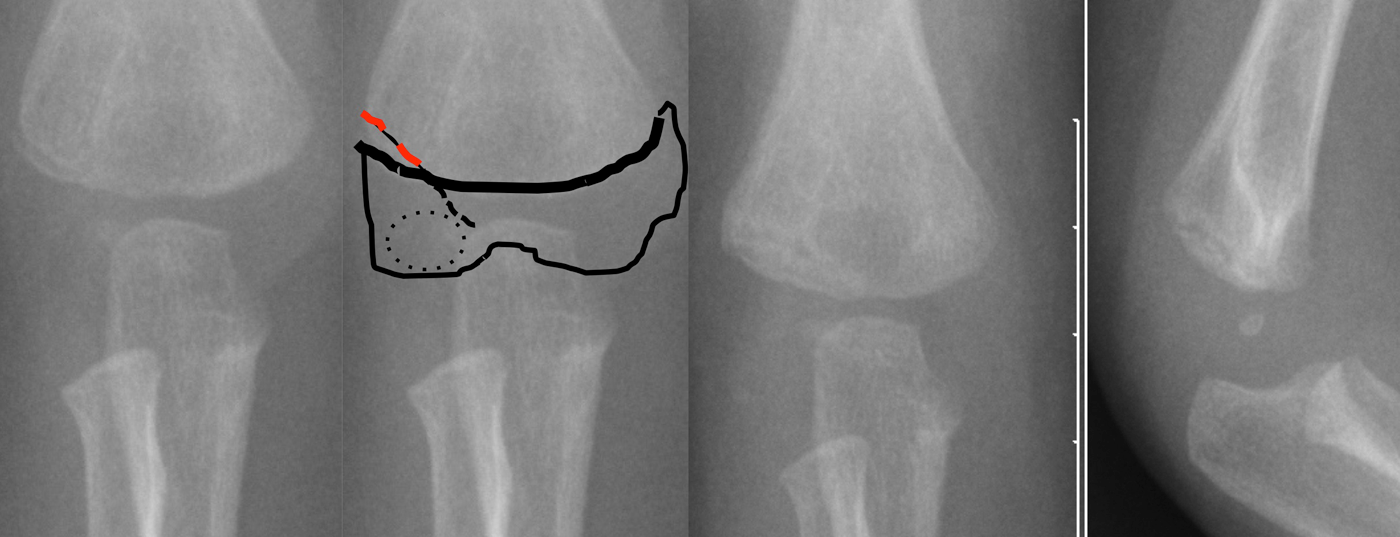

Fracturas en el codo (Fig. 2)

Fractura del cóndilo radialis: Se trata de una lesión que puede subestimarse debido a la osificación completa tardía del capítulo con el húmero distal.

Hay que tener en cuenta que el curso de la fractura puede extenderse hasta la articulación y, por lo tanto, una fractura principalmente no desplazada también puede luxarse secundariamente. Por lo tanto, es urgente realizar una radiografía de control sin escayola al cabo de cuatro o cinco días para comprobar la posición. Las luxaciones <2 mm pueden tratarse de forma conservadora con una escayola en la parte superior del brazo (Fig. 3), de lo contrario es necesaria una reducción abierta y una fijación con agujas de Kirschner.

Fractura del epicóndilo cubital: Se trata de una lesión por avulsión de los flexores del antebrazo o una avulsión directa tras una luxación de codo. La progresión de la fractura es a través de la articulación, por lo que a veces un epicóndilo humeral cubital “normal” puede ser malinterpretado como fracturado por el inexperto. La tracción de los flexores suele distalizar el fragmento de fractura del húmero, por lo que en este caso no es infrecuente que esté indicada la reducción abierta y la osteosíntesis con tornillos.

Si la fractura sólo está ligeramente dislocada, puede tratarse de forma conservadora con una escayola en la parte superior del brazo.